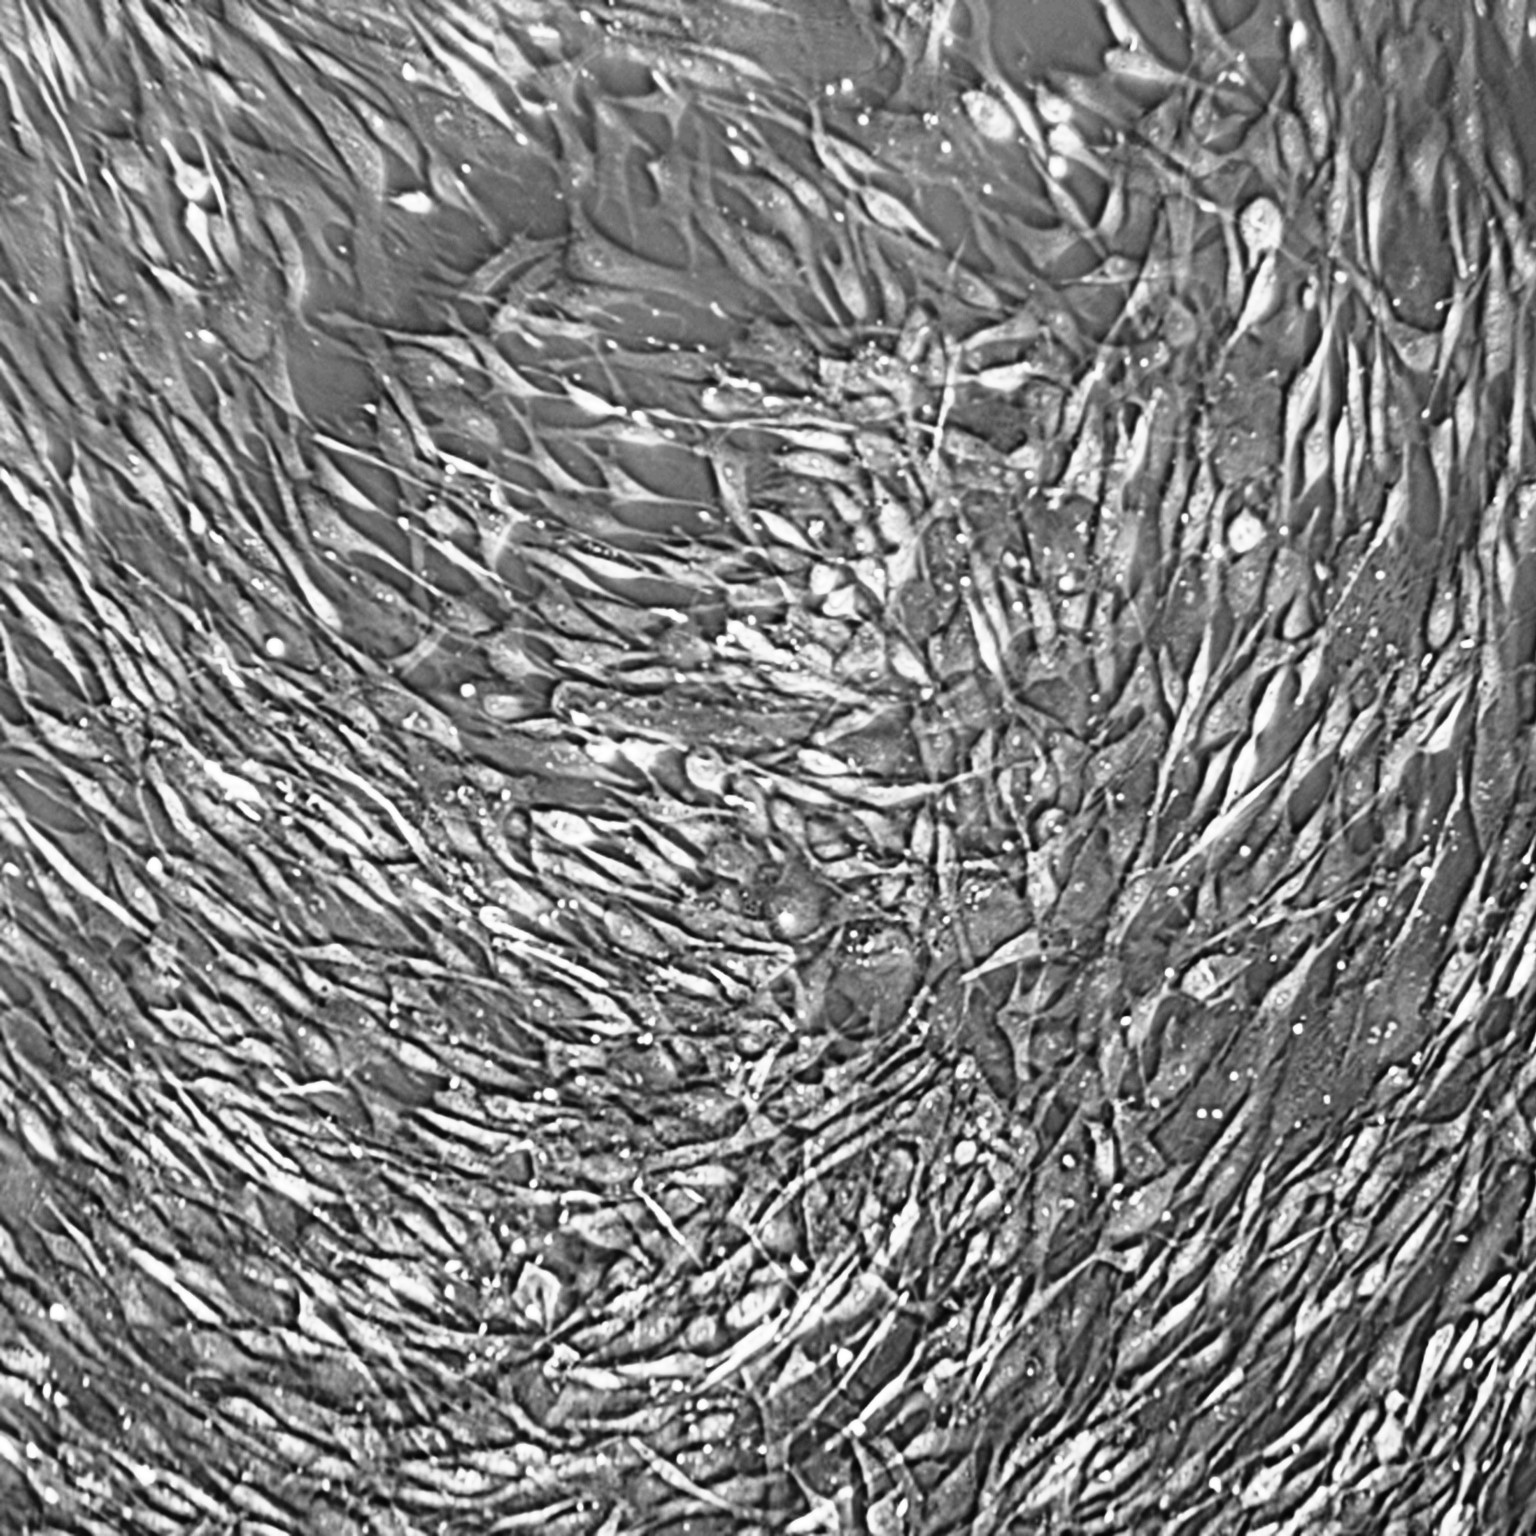

Lifeline® Normal Human Bronchial/Tracheal Epithelial Cells (HBTEC), when grown in Lifeline®BronchiaLife™ Medium, provide an ideal serum-free culture model for the accurate studies of toxicity, cystic fibrosis, asthma, pathogenesis, pharmacology or airway wound healing.